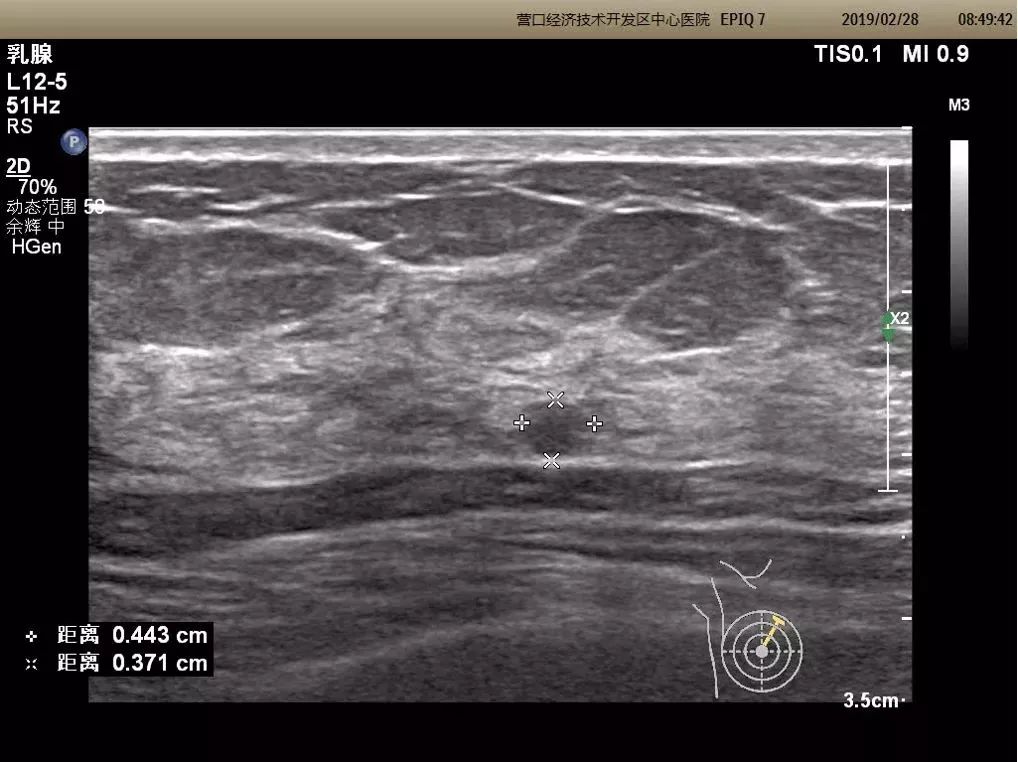

浅表器官三维超声成像

可显示甲状腺、乳腺结节的三维立体图像,可多角度、多切面观察病灶,对选定区域切割成像,能够清晰显示结节的空间位置、内部细微结构及内部血管树构型,同时进行连续性观察和定量和半定量测量。对肿块的良恶性鉴别提供较大帮助。

二维成像

三维成像